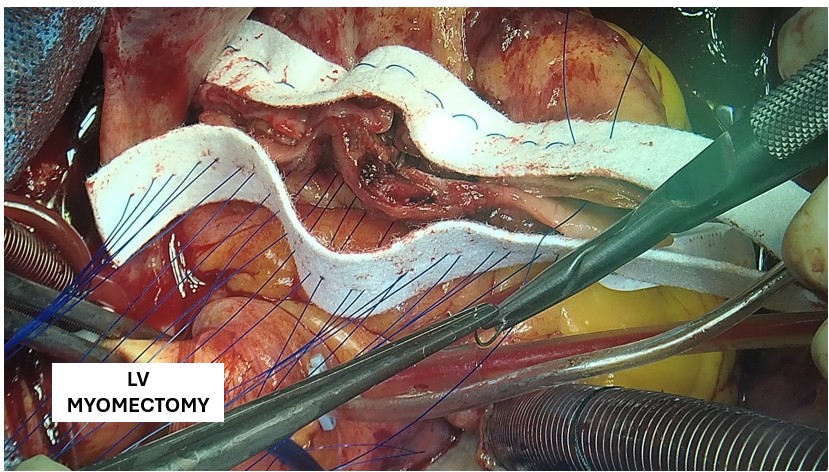

A covered stent was deployed in the distal LAD in an attempt to seal the coronary perforation; however, angiography showed that the Type III perforation persisted despite the intervention. Additional balloon inflation within the stent was performed, but the leakage could not be completely sealed. The patient remained hemodynamically stable without signs of cardiac tamponade or pericardial effusion. The following day, repeat coronary angiography was conducted to reassess the condition, which confirmed persistent contrast extravasation from the LAD into the left ventricular cavity, indicating the formation of a coronary–ventricular fistula. Given the hemodynamic significance and the risk of progressive left ventricular dysfunction due to continuous shunting, a multidisciplinary decision was made to proceed with surgical correction. The patient subsequently underwent successful LAD–LV fistula patch repair combined with. Surgical repair remains the definitive management for such cases, and early recognition with timely intervention is crucial to restore cardiac function and prevent irreversible myocardial damage.

The patient underwent successful surgical patch closure of the LAD–LV fistula along with ventricular reconstruction to restore myocardial integrity. The postoperative recovery was smooth and uneventful, with stable hemodynamics throughout hospitalization. Follow-up echocardiography demonstrated significant improvement in LVEF to 53%, and she remained asymptomatic during subsequent outpatient follow-up